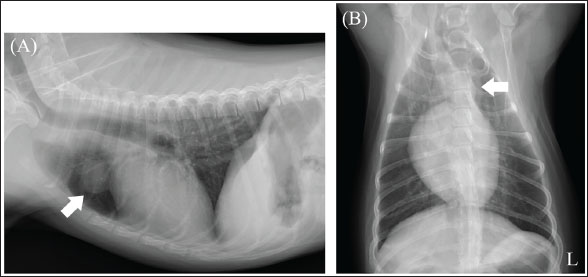

A neutered 9-year-old male Papillon weighing 3.5 kg was referred to the Okayama University of Science Veterinary Medical Teaching Hospital for examination and treatment of an incidentally discovered mass in the cranial intrathoracic cavity during regular medical checkups. The dog had no clinical signs and was in good general condition. However, a mass in the cranial thoracic region was detected by chest radiography. Blood tests showed no hypercalcemia, and arterial blood gas analysis showed no problems (Table 1). Polycythemia, slight hypernatremia, and hyperchloremia, which may be related to dehydration, were also observed. A chest X-ray revealed a mass of approximately 20 mm in the cranial intrathoracic cavity and mild expansion of the mediastinum (Fig. 1). The tumor-associated syndromes, such as megaesophagus and myasthenia gravis, were not observed. Computed tomography (CT) was performed under general anesthesia (Aquilion Lightning; Canon Medical Systems Co., Tokyo, Japan). Iopamidol (Oypalomin 300, Fuji Pharma, Japan) was used as a contrast medium (injection volume, 2.5 ml/kg [750 mgI/kg]; injection time, 15 seconds). Precontrast, arterial phase, venous phase, and equilibrium phase scans were obtained. The cranial intrathoracic mass (length, width, and height of 18.3, 16.0, and 18.6 mm, respectively) was a solitary lesion within the cranial mediastinum (Fig. 2). The mass was well demarcated, and there was no evidence of invasion into the surrounding blood vessels. The CT values of the mass were 43.2, 50.6, 113.1, and 102.2 HU for the precontrast, arterial, venous, and equilibrium phases, respectively (Fig. 2). These contrast enhancement effects were a preliminary diagnosis that the mass was a thymoma (Von Stade et al., 2019). Enlarged surrounding lymph nodes or distant metastasis were not detected. Due to the small size of the mass and its absence from the thoracic cavity margin, preoperative pathological examination could not be performed. Based on the CT results, the mass was provisionally diagnosed as a thymoma. The thymoma volume was measured from the length, width, and height by computed tomography using the elliptical volume formula. The cranial intrathoracic volume was measured using a 3D image analysis software (Ahmics-VAZE, PetCommunications Co., Ltd., Osaka, Japan). The cranial intrathoracic region between the first and fourth sternum at the beginning of the cranial intrathoracic cavity was assumed to be the surgical space for VATS-T (Fig. 3). The dorsal cephalic end was designated as the point where the first sternum extends perpendicularly and joins the thoracic vertebrae, and the dorsal caudal end was designated as the point where the fourth sternum extends perpendicularly and joins the thoracic vertebrae. This region was extracted and its volume was measured using the 3D volume rendering function by Ahmics-VAZE. The ratio of thymoma volume to cranial intrathoracic volume (T/CI ratio) was calculated as follows: thymoma volume/cranial intrathoracic volume × 100). The thymoma volume was 2.3 cm3, the cranial intrathoracic volume was 97.7 cm3, and the T/CI ratio was 2.4%. The thymoma volume was calculated using the approach in a previous report of two cases that described the thoracoscopic resection of thymomas (Mayhew and Friedberg, 2008). We also calculated the cranial intrathoracic volume for the dog, as it was of the same breed and weight as the two reported cases. Subsequently, we calculated the T/CI ratio. In previous reports, the thymoma volumes were 9.5 cm3 and 36.6 cm3, respectively, and the cranial intrathoracic volume was 892.8 cm3. The T/CI ratios were 1.1% and 4.1%, respectively.

Fig. 2. Chest computed tomography (CT) imaging. (A) Pre-contrast phase. (B) Arterial phase. (C) Venous phase. (D) The equilibrium phase. The cranial chest mass (length, width, and height of 18.3, 16.0, and 18.6 mm, respectively) was a solitary lesion within the cranial mediastinum. The lesion was well demarcated and showed no signs of invasion into the surrounding blood vessels. The CT values of the lesion were 43.2 HU for the pre-contrast phase (A), 50.6 HU for the arterial phase (B), 113.1 HU for the venous phase (C), and 102.2 HU for the equilibrium phase (D) (L): Left side.